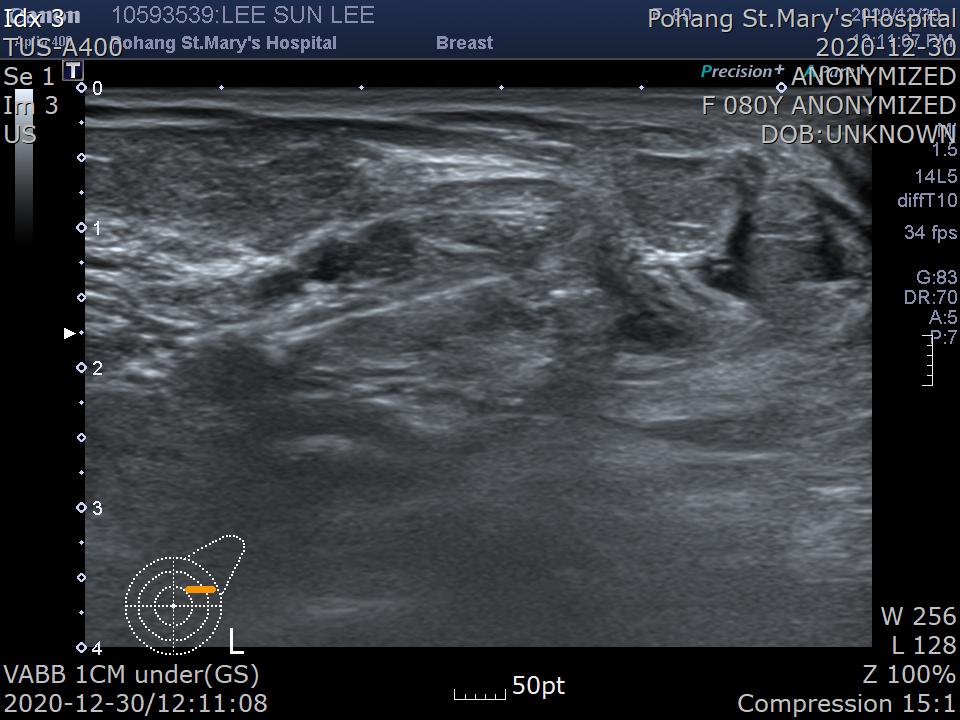

계속 종양을 절제합니다.

VABB 프로브(probe)만 보이고 probe 위쪽으로 종양이 완전히 절제된 소견 입니다.